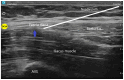

The incidence of hip fractures has continued to increase as life expectancy increases. Hip fracture is one of the leading causes of increased morbidity and mortality in the geriatric population. Early surgical treatment (<48 h) is often recommended to reduce morbidity/mortality. In addition, adequate pain management is crucial to optimize functional recovery and early mobilization. Pain management often consists of multimodal therapy which includes non-opioids, opioids, and regional anesthesia techniques. In this review, we describe the anatomical innervation of the hip joint and summarize the commonly used peripheral nerve blocks to provide pain relief for hip fractures. We also outline literature evidence that shows each block's efficacy in providing adequate pain relief. The recent discovery of a nerve block that may provide adequate sensory blockade of the posterior capsule of the hip is also described. Finally, we report a surgeon's perspective on nerve blocks for hip fractures.

Keywords: fascia iliaca block; lateral femoral cutaneous nerve; pericapsular nerve group (PENG) block.